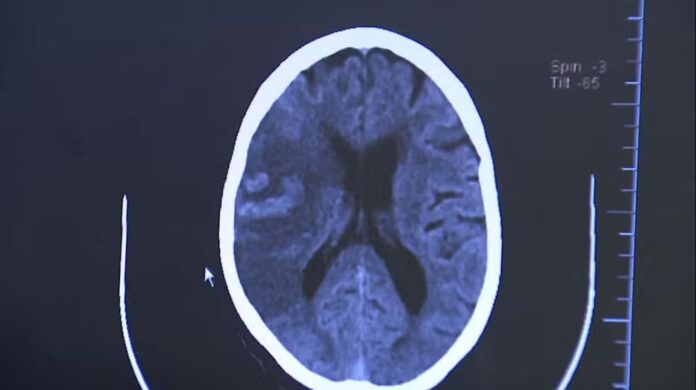

Tipos de AVC

- Isquêmico (85% dos casos) – ocorre quando há entupimento de um vaso sanguíneo que leva sangue ao cérebro. Está ligado à pressão alta e a doenças cardíacas, como a fibrilação atrial, que pode formar coágulos e bloquear artérias cerebrais.

- Hemorrágico (15% dos casos) – acontece quando há rompimento de um vaso, provocando sangramento no tecido cerebral. É menos comum, mas mais grave, com risco elevado de sequelas e morte.